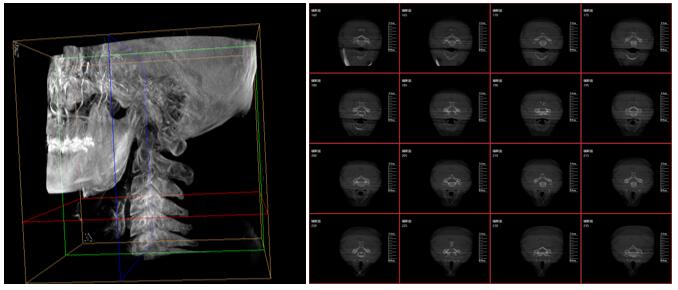

PLX7500三維成像圖片

這款新型三維C型臂—PLX7500集成手術導航和手術機器人接口,可無線傳輸三維重建的圖像數據至導航設備,無需額外手動注冊步驟,實現術中圖像的實時引導規劃,輔助醫生精準定位手術器械和植入物,為實現手術室的數字化和智能化拓展提供可能。

采用30cmx30cm的動態平板探測器,輸出高分辨率、大尺寸的二維、三維圖像。超高16比特灰階度,高動態范圍清晰顯示植入物的位置和輪廓。

強大的圖像后處理功能軟件,自動調整比較好的圖像窗寬窗位,顯著降低螺釘的金屬偽影,降低圖像區域噪點,進一步優化圖像品質。